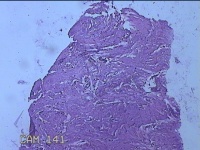

右膝前瘢痕增生组织

性别

女

年龄

38岁

临床诊断

右膝前瘢痕增生

一般病史

右膝前外伤后瘢痕增生4年余。

标本名称

大体所见

灰白粉红色组织6.5x5x1.8cm一块,表面光滑,切面灰白粉红色,质软。